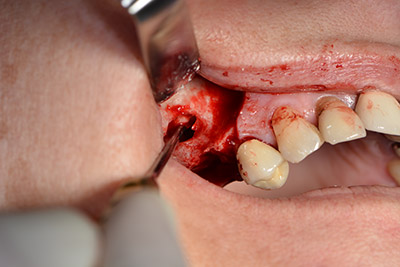

The classic incision (crestal, buccal relief) and the preparation of the mucoperiosteal flap enabled a good overview.

The fenestration was prepared at 35,000 rpm and then the nasal mucosa were prepared in the cranial direction (Fig. 13 to 14).

The implant was then placed and the bone built up. In this case, because of the size of the augmentation region, autologous bone chips, harvested with an osseous trap as drilling chips from implantation 16 and fenestration 14, were mixed with bone replacement material.